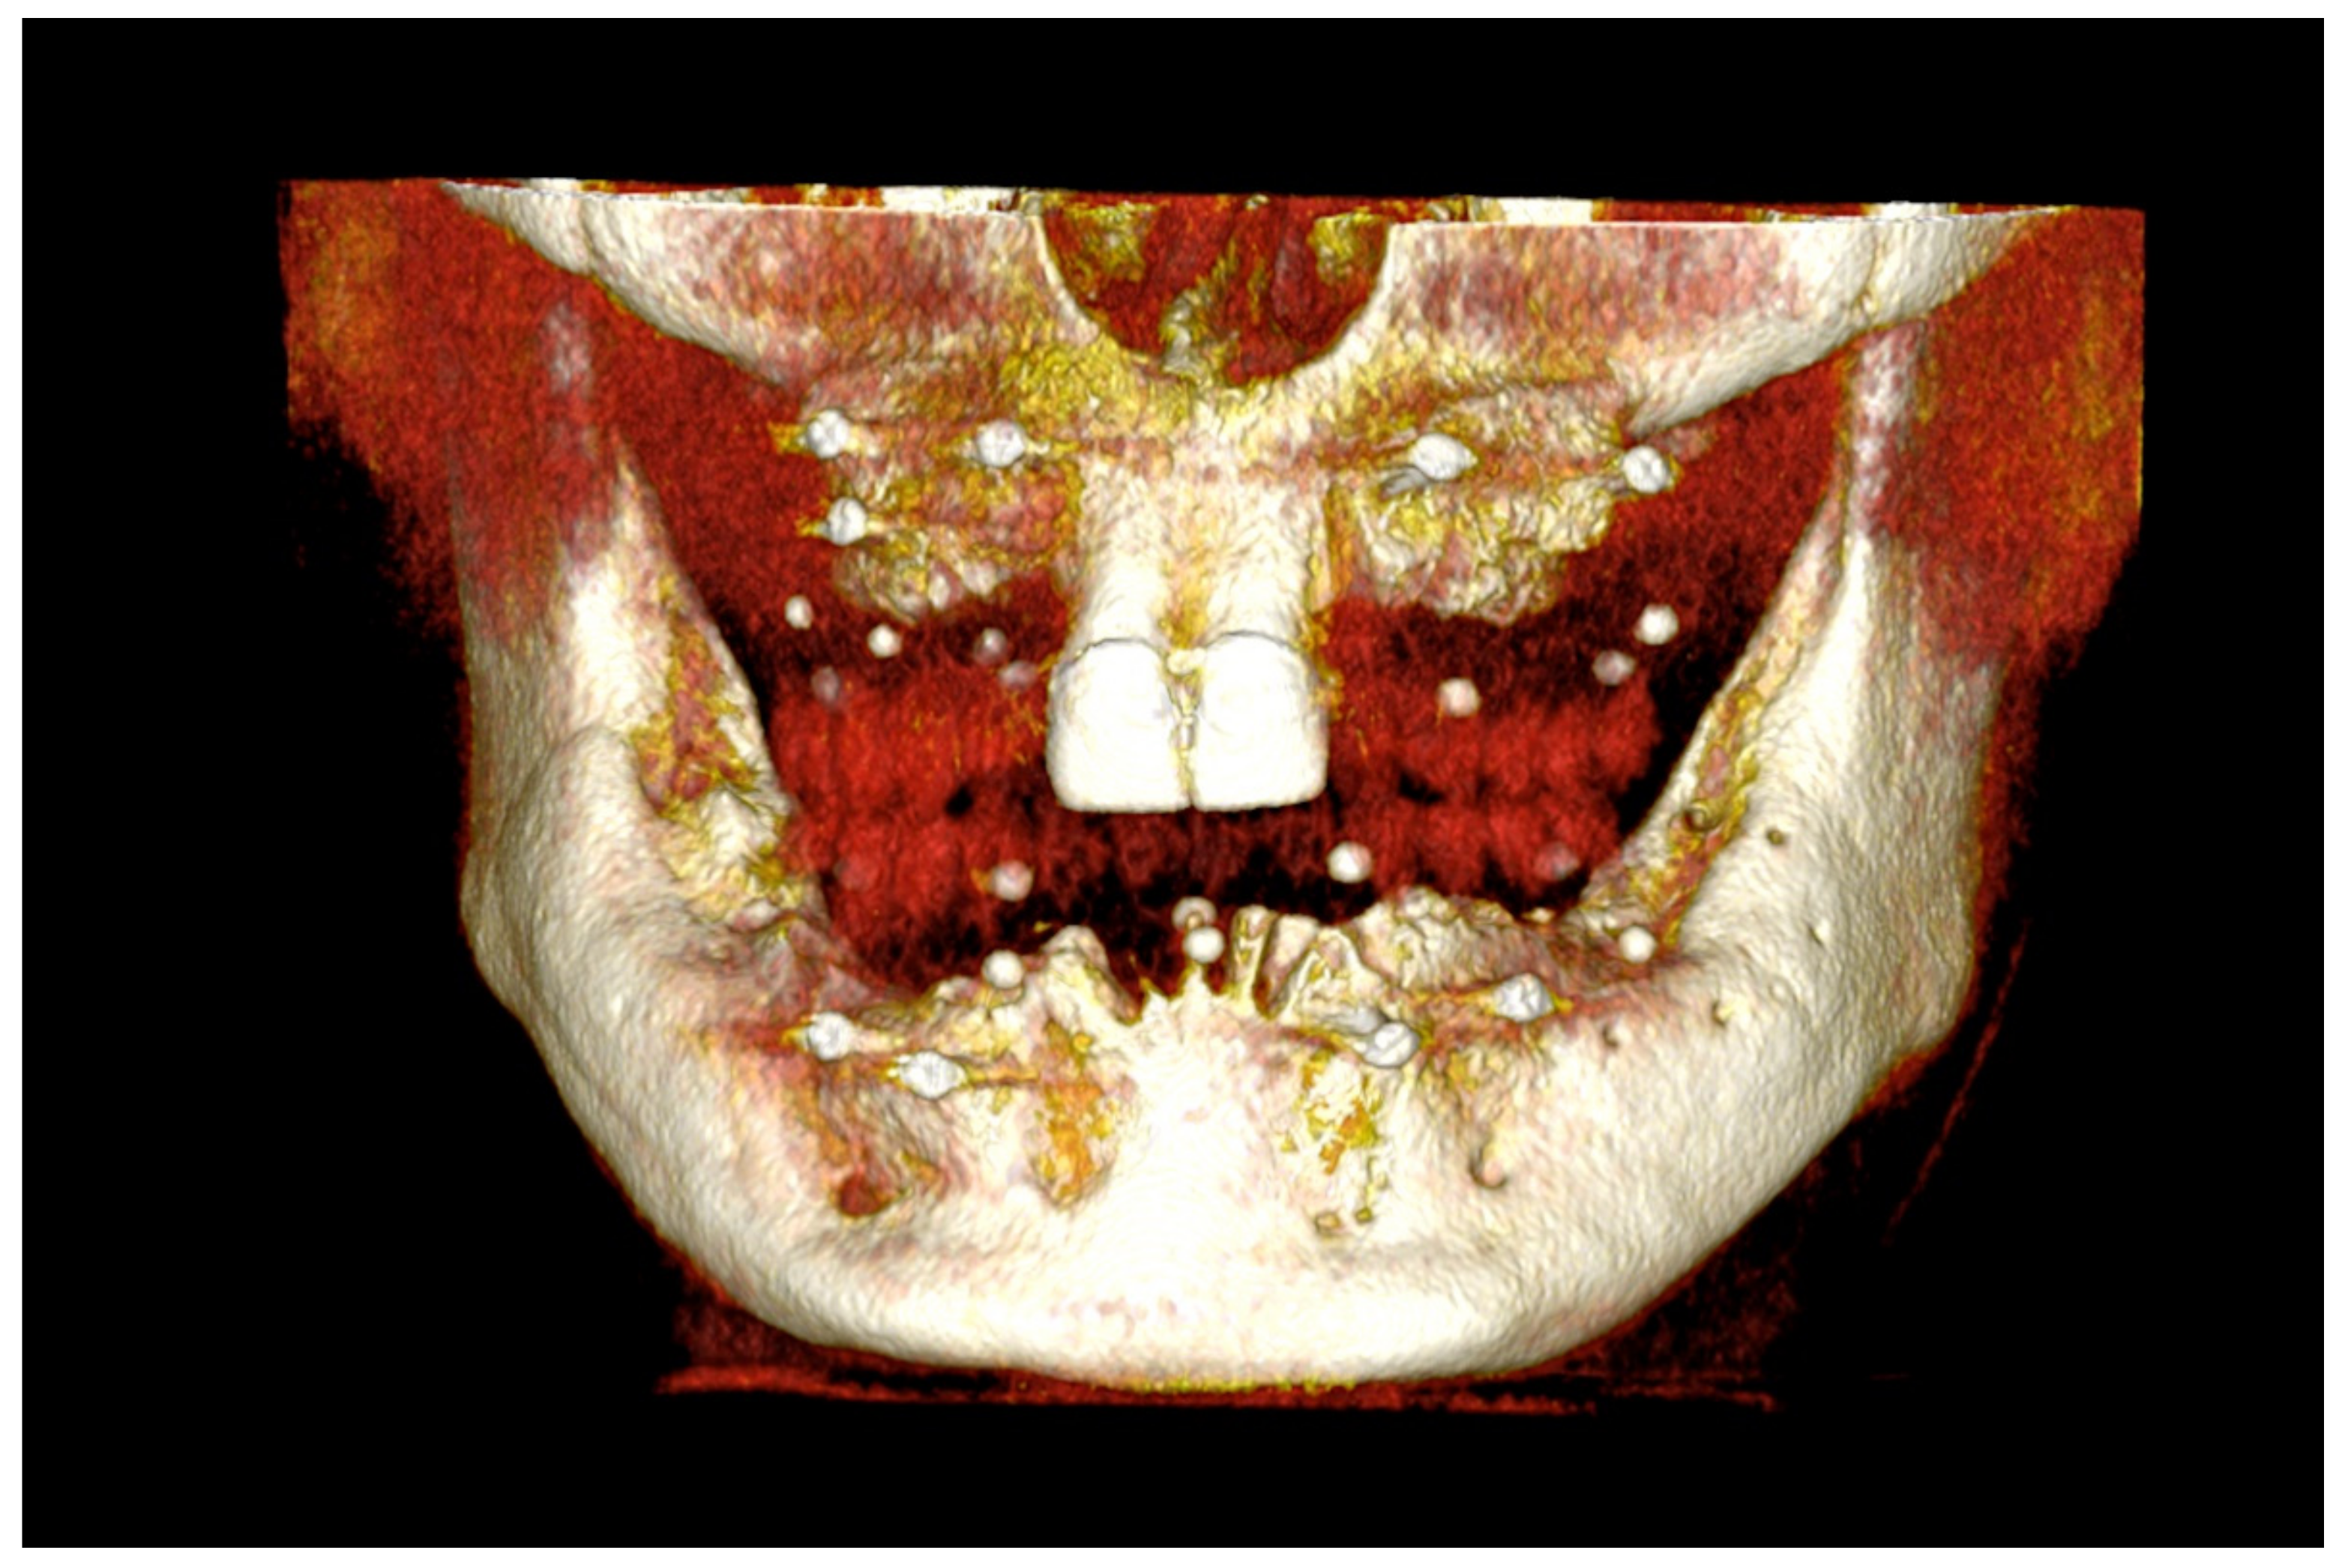

Figure 16.

Three-dimensional (3D) CBCT scan images with the patient wearing the planned prosthesis.

Figure 17.

Three-dimensional (3D) CBCT scan images of the prosthesis equipped with integrated radiopaque reference spheres scanned separately.

Figure 31.

Three-dimensional (3D) CBCT scan images of the edentulous mandible with the patient wearing the provisional prosthesis and 3D images of the prosthesis equipped with integrated radiopaque reference spheres scanned separately.